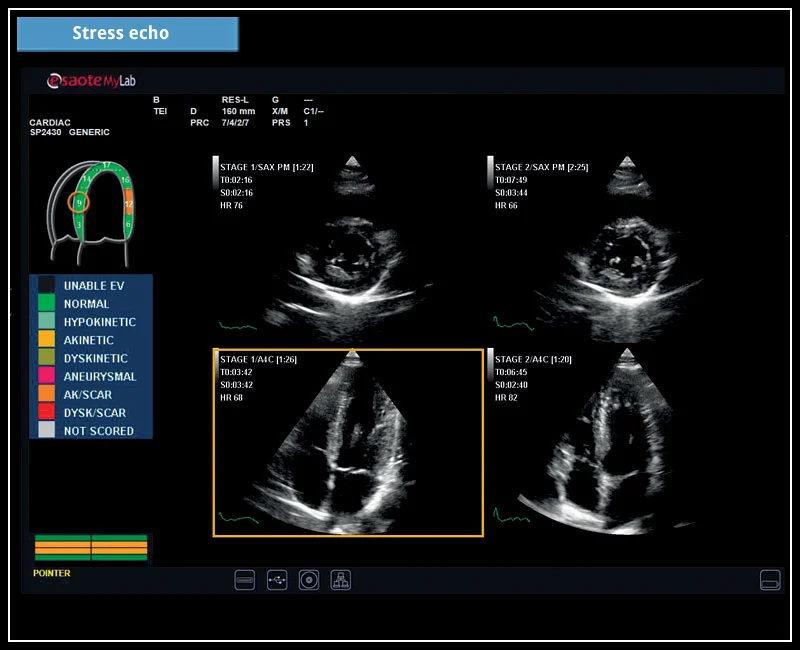

Das neue MyLab™X6 von Esaote macht Ihren Workflow so effizient und reibungslos, dass es nicht nur die Produktivität erhöht, sondern auch Ihre klinischen Leistungen verbessert. Es deckt alle klinischen Anforderungen von abdominalen bis zu endokrinologischen Anwendungen ab, um eine sichere Diagnose zu stellen und die bestmögliche Therapie und Nachsorge zu bieten.